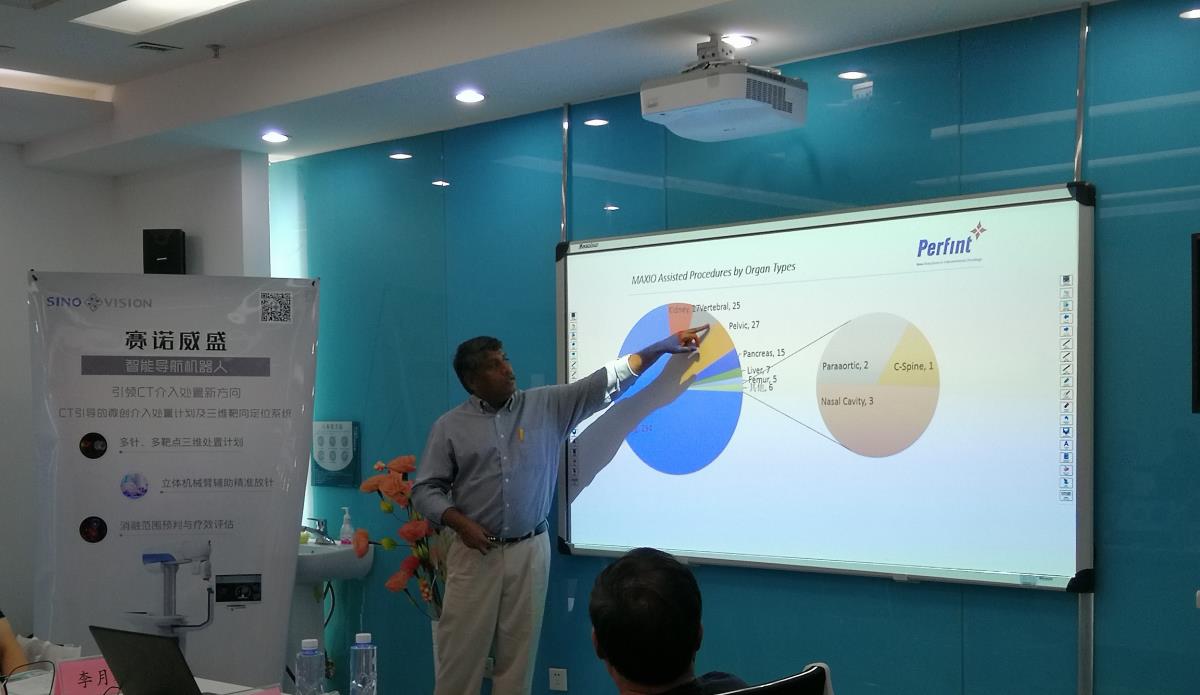

Perfint CEO Nandu先生介绍了导航机器人全球临床应用情况,包括临床手术种类,与徒手穿刺临床治疗效果对比等。并对 404 例手术做了真实临床数据统计,一针到位平均误差在1.5mm,计划处置时间降低到7分钟。大幅减少了布针调整次数,降低了扫CT描验证的次数,提高了手术的精准度和安全性。

Nandu介绍导航机器人全球使用情况